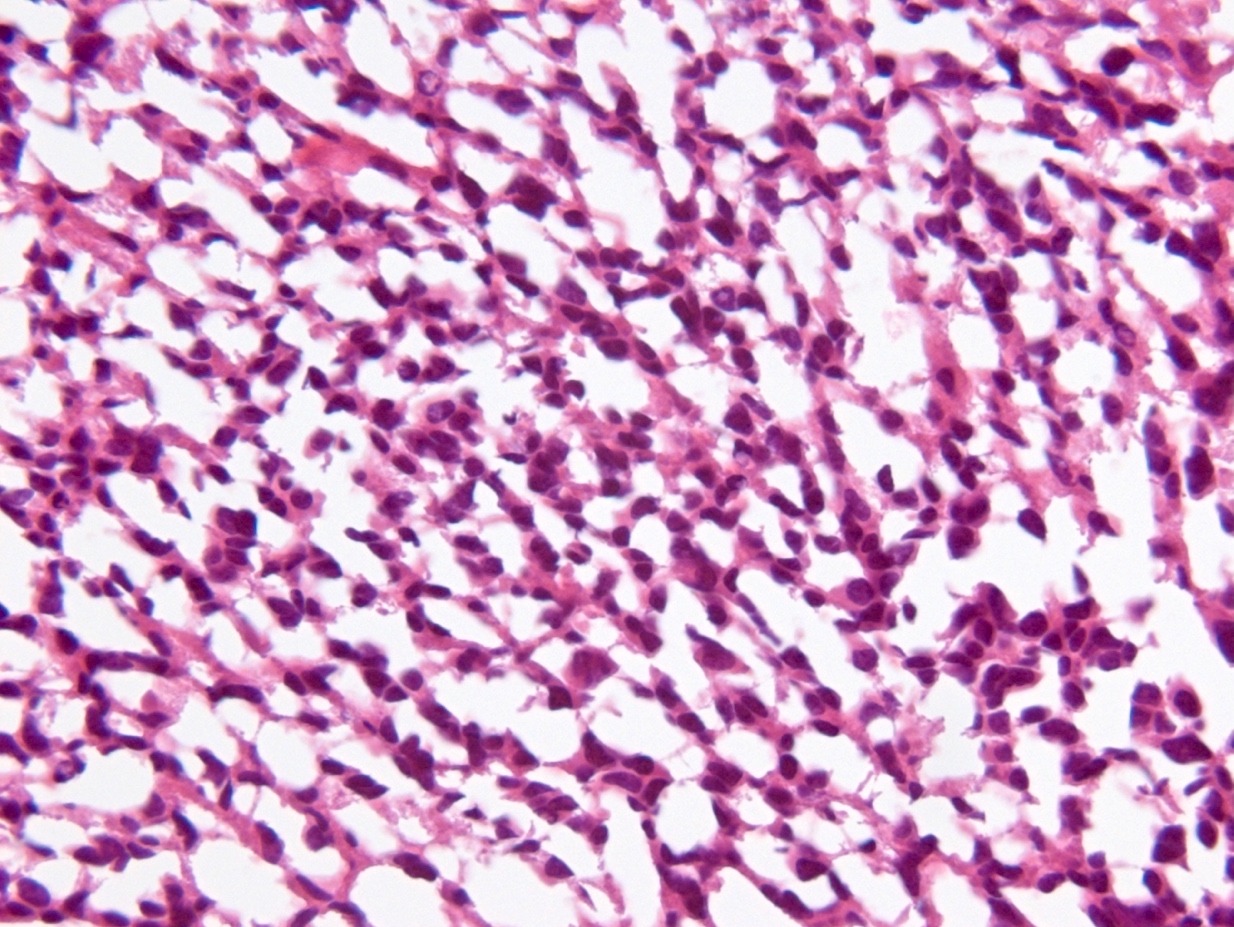

Microscopic (histologic) description

- Diffusely infiltrating tumor cells with oval to elongated astrocytic nuclei and varying appearance of tumor cytoplasm and fibrillar glial processes (Acta Neuropathol 2015;129:789)

- At the periphery, tumor cells may infiltrate in a diffuse single cell pattern, often with entrapped neurons and axons

- Cellular morphology is variable, even within a single tumor

- Commonly there is a mix of cells with elongated nuclei and fine fibrillar processes, cells with eccentric nuclei and glassy eosinophilic cytoplasm (gemistocytes), larger pleomorphic cells and small cells with scant cytoplasm

- May show oligodendroglioma-like areas

- Myxoid background and microcyst formation may be present

- Variable mitotic activity, cellularity and nuclear atypia depending on CNS WHO grade

- In small biopsy specimens, the presence of 1 mitosis may be sufficient for a CNS WHO grade 3 diagnosis, while the presence of a few mitotic figures in a large resection would not be sufficient for grade 3 designation (Acta Neuropathol 2020;139:603)

- Presence of necrosis or microvascular proliferation would be consistent with a CNS WHO grade 4 designation

Microscopic (histologic) images

Contributed by Eman Abdelzaher, M.D., Ph.D., John DeWitt, M.D., Ph.D. and Meaghan Morris, M.D., Ph.D.